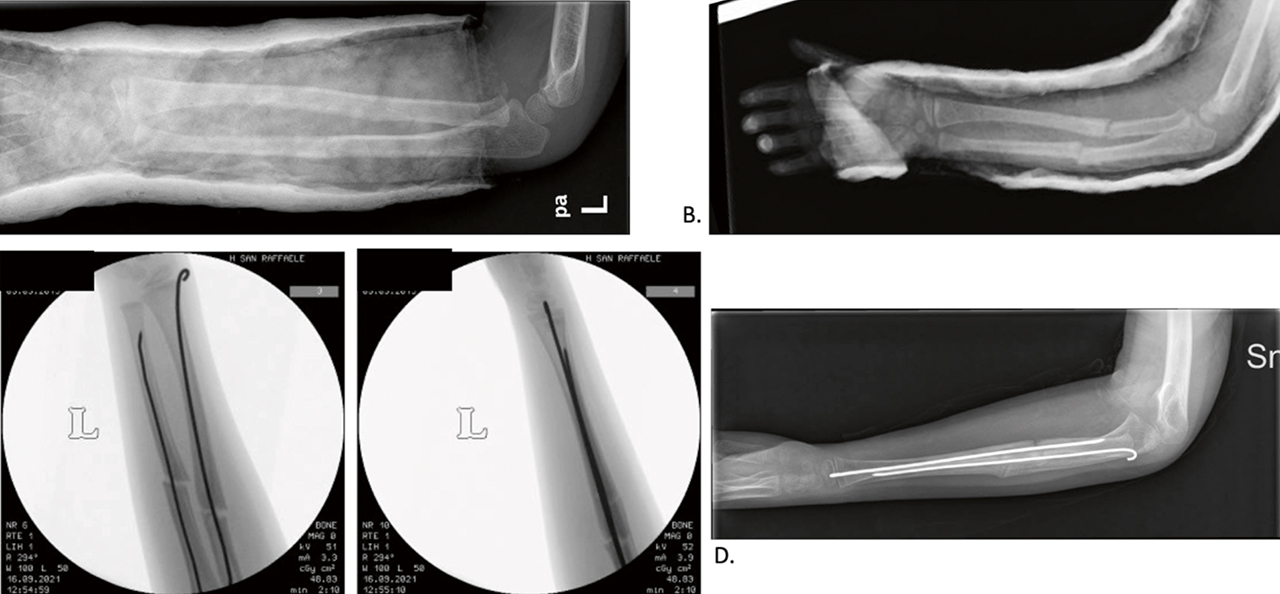

Le indicazioni al trattamento chirurgico delle fratture di avambraccio sono limitate alle fratture instabili (es. fratture biossee con rima obliqua allo stesso livello tra radio e ulna 10), alle fratture irriducibili, alle fratture esposte e in quei casi in cui si verifica perdita della riduzione (Fig. 2).

Il trattamento chirurgico mira a una stabilizzazione efficace con minimo danno ai tessuti molli, per mantenere un’adeguata riduzione fino a completa consolidazione della frattura. Il trattamento chirurgico più comune è la sintesi endomidollare elastica (ESIN). Il trattamento chirurgico con ESIN, che ha visto espandere le sue indicazioni e la sua applicazione negli ultimi 30 anni, nonostante i buoni risultati complessivi che fornisce va comunque limitato alle corrette indicazioni: fratture instabili o potenzialmente instabili, fratture in adolescenti oltre i 12 anni dove il rimodellamento prevedibile è limitato, fratture esposte, alto rischio di sindrome compartimentale, rifratture. La tecnica ESIN prevede l’applicazione di chiodi endomidollari elastici in grado di mantenere la riduzione sfruttando la pressione su diversi punti del canale endomidollare. Il planning prevede l’utilizzo di un chiodo per il radio e uno per l’ulna. L’impianto nel radio avviene sempre per via retrograda dalla metafisi distale, mentre per l’ulna si accede dalla faccia laterale o mediale della metafisi prossimale o dalla metafisi distale a seconda della sede di frattura 10. Per l’accesso dalla metafisi distale del radio sono state descritte due modalità: l’accesso dalla faccia laterale della metafisi radiale oppure l’accesso dalla faccia dorsale della metafisi, a livello del tubercolo di Lister. Entrambi gli accessi richiedono grande premura nei confronti del ramo sensitivo dorsale del nervo radiale e del tendine estensore lungo del pollice. In entrambi i casi è consigliato eseguire una piccola incisione cutanea seguita da accurata dissezione dei piani profondi fino alla superficie ossea, in modo da individuare e proteggere le suddette strutture anatomiche. Non esistono evidenze su quale sia il segmento osseo da trattare per primo: solitamente viene trattato prima il radio in quanto risulta essere il segmento più difficile da ridurre. Si consiglia di scegliere un chiodo di diametro pari a 2/3 del canale diafisario, misurato al suo terzo medio. La procedura permette la riduzione e la stabilizzazione della frattura con due piccoli accessi cutanei, rispettando al massimo i tessuti molli e il focolaio di frattura. Al termine dell’intervento le code dei chiodi vengono tagliate vicino al piano osseo e lasciate sottopelle. Lasciare i chiodi fuori dalla pelle permette la loro rimozione ambulatoriale ma può esporre al rischio di infezione, rallentando il recupero funzionale.

Altri sistemi di sintesi utilizzati i fili di Kirschner, i fissatori esterni e le placche. L’utilizzo dei fili di Kirschner trova ancora la sua indicazione nelle fratture del terzo distale della diafisi, al limite con le fratture metafisarie, dove l’applicazione degli ESIN risulta poco agevole e fonte di possibili perdite di riduzione secondarie. La fissazione esterna riveste un ruolo maggiore nelle fratture esposte. Le placche, utilizzate a cielo aperto come nell’adulto, sono destinate al trattamento degli esiti. Nella maggior parte dei casi non è necessario un lungo periodo di immobilizzazione dopo l’intervento, anzi, alcuni autori incoraggiano la mobilizzazione attiva e passiva precoce. I controlli RX vengono eseguiti a quattro settimane e a tre mesi dalla frattura. La rimozione dei chiodi può essere pianificata in un tempo variabile tra i 6 e i 18 mesi dalla frattura.